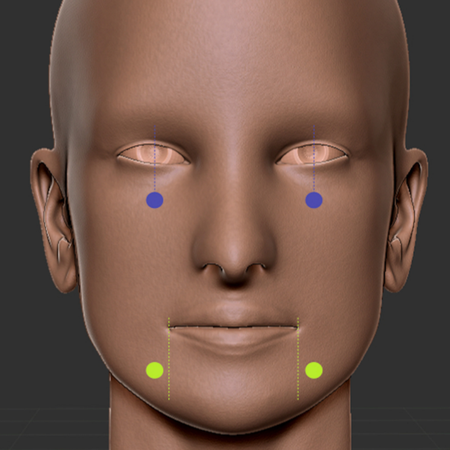

Introdução: As alterações somatossensoriais continuam sendo uma desvantagem da cirurgia ortognática (CO). Objetivo: Este estudo avaliou os limiares mecânicos e de dor após a CO. Métodos: Estudo transversal com grupo controle (GC, pareado por sexo e idade), incluindo pacientes submetidos a CO e pacientes sem alterações somatossensoriais. O grupo que compreendeu os pacientes submetidos a CO (GO) foi dividido em GO1 e GO2, de acordo com a mediana de acompanhamento pós-operatório em...

Introduction: Somatosensory changes remain a disadvantage of orthognathic surgery (OS). This study evaluated mechanical and pain thresholds after OS. Methods: This cross-sectional study with control group (CG, paired by sex and age), included OS patients and patients without somatosensory changes. The orthognathic group (OG) was divided in OG1 and OG2, according to the median of postoperative follow-up in months. Mechanical detection threshold (MDT), mechanical pain threshold (MPT) and...